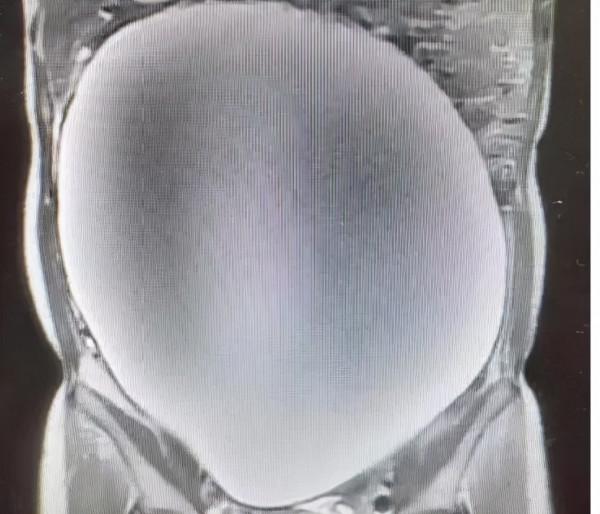

她急忙來到廈門市第五醫院求診,經腹部磁共振一掃檢,肚子裡竟然藏了個巨大的卵巢腫瘤,直徑足足30CM大。

幸運的是,經過術中快速病理,發現該腫瘤為良性腫瘤,醫生成功地做了手術將腫瘤切除了。